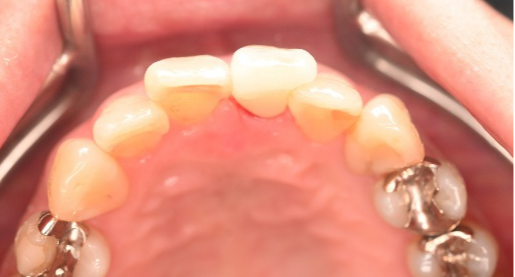

治療内容

前歯3本にオールセラミック冠を被せて、歯並び及びすり減った歯を審美的に回復しました。歯ぎしりが強くあることがわかりましたので、マウスピースを使ってもらう事にしました。

所感

一番オススメな方法は、矯正をし、歯並びを整えた後、すり減って形が変わってしまった歯に被せ物をすることをお話ししました。患者さんは、3本に被せ物をすることにより歯並びをきれいにすることを希望されました。

治療後、「曲った前歯が長年コンプレックスでした。セラミックの歯の色合いや形が自然な仕上がりで、相談して本当に良かったです!神経を抜くこともなく治療ができ、予定よりも低料金にしてもらえたのがありがたかった。先生も、歯科衛生士さんも事務の人も皆、優しく寄り添った対応をしてくれました。ありがとうございました!」と、とても嬉しいお話しをしてくださいました。

オールセラミック冠3本:¥93,500(生活歯)×3本=¥280,500(税込)

Before

After